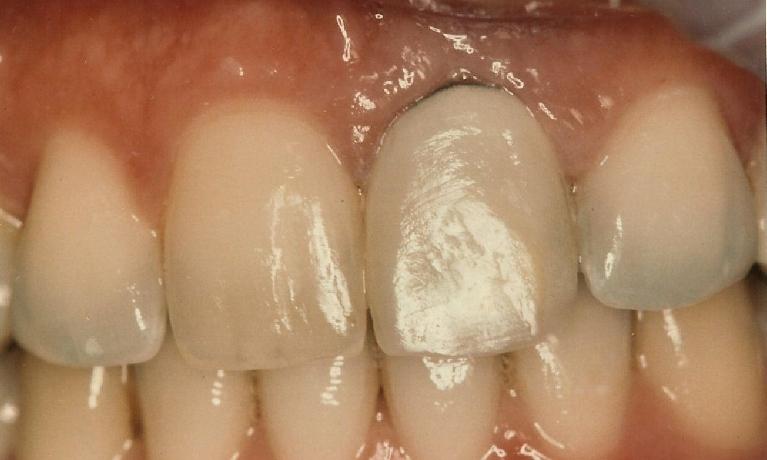

Before

After

Repair of fractured incisor with composite resin.

This young Yale student fractured her two front teeth a few days after arriving in New Haven to begin her graduate school. She had recently bleached her lower teeth before leaving home.

Composite resin was bonded to the fractured area, and her treatment was completed within an hour.